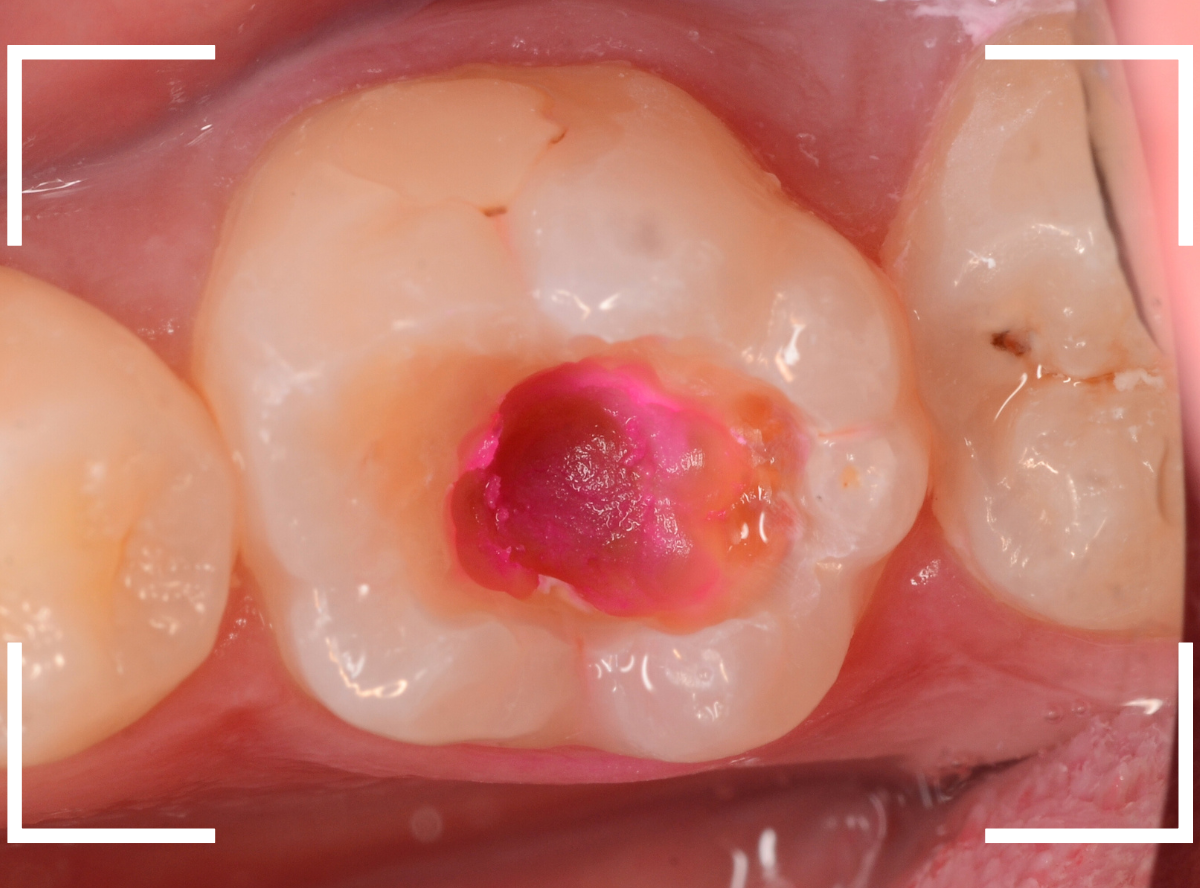

ある程度、虫歯を除去したところで、う蝕検知液で確認します。

真っ赤に染まり、まだ虫歯が取り切れていないのがわかります。

神経まで近づいてきたので、慎重に虫歯を除去します。

赤く染まっている部分が、まだ虫歯が残っている箇所です。

歯の神経が近いので、余分に削りすぎないように、より慎重に虫歯を除去します。